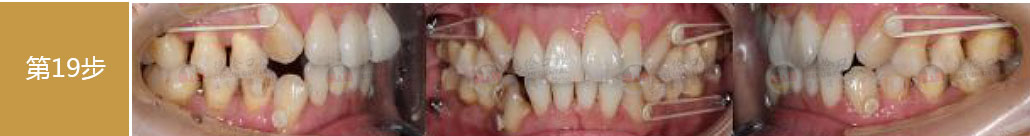

矯治采用兩種不同的厚度的膜片(牙套),發揮兩種不同膜片的各自優勢,在有效的作用時間內,矯治效率、矯治目標達成和舒適度方面較普通隱形矯正方式有明顯提升。

厚薄兩種矯治器,每周替換有利于牙齒位置的準確控制